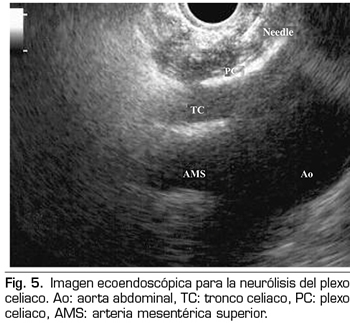

NEURÓLISIS ECOENDOSCÓPICA DEL PLEXO CELIACO

La ecoendoscopia ofrece la ventaja de una mayor visualización del plexo celiaco a corta proximidad, permitiendo una mayor precisión y seguridad en la administración del agente neurolítico y evitando la inyección en estructuras vasculares mediante el uso del Doppler (37) (Figura 5). No obstante, los trabajos que apoyan la neurólisis ecoendoscópica, considerada al igual que la técnica percutánea como una terapia de rescate, están limitados a estudios retrospectivos no controlados (38). Pauli y cols. publicaron un metanálisis que concluye que esta técnica consigue una reducción del dolor del 80 % en pacientes con cáncer de páncreas (39). Algunos estudios muestran un ligero descenso en el consumo de opioides, pero sin una fuerte evidencia científica.

En cuanto a los efectos adversos, se limitan a una serie de publicaciones retrospectivas y series de casos, estando descritos la hipotensión (11 %), la diarrea (18 %) y el dolor abdominal transitorio (1,5 a 8 %) (37). Teóricamente, esta técnica es más segura, con su abordaje anterior a través de la pared gástrica y paso directo de la aguja al plexo visualizando los vasos, sin tener que atravesar el espacio retrocrural (41). Aun así, también se han publicado complicaciones fatales con esta técnica. Gimeno-García y cols. (42) describieron la primera complicación de trombosis y vasoespasmo de la arteria celiaca que produjo una isquemia multiorgánica y la muerte del paciente. Desde entonces esta complicación se ha publicado en otros 2 trabajos, que también acabaron en muerte (43,44). Otros efectos adversos descritos son el sangrado retroperitoneal y 2 casos de paraplejia.

Dentro de las contraindicaciones relativas a esta técnica se encuentran: la presencia de varices gástricas o esofágicas −ya que aumentan el riesgo de sangrado−, una anatomía desestructurada, la invasión tumoral directa del plexo, y las malformaciones congénitas del tronco celiaco o de la arteria mesentérica superior.